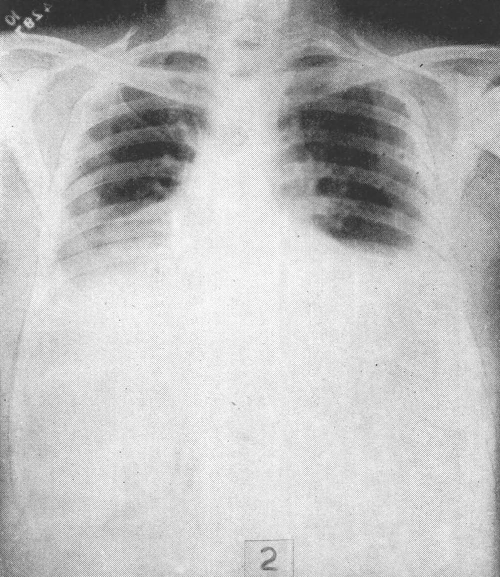

| Lastra di Pz. con beri beri umido: ascite e versamenti pleurici |